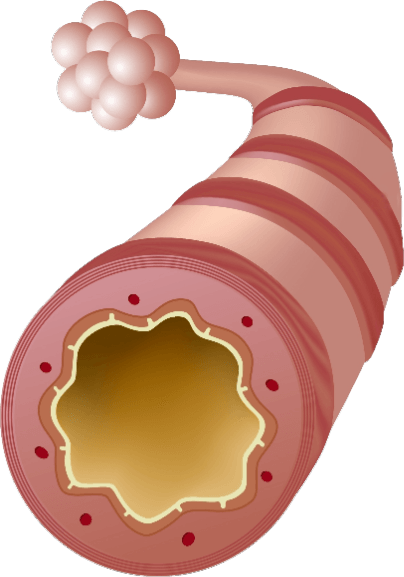

MECHANISM OF ACTIONS (MOA)

EA 575® is also unique to help improve respiratory function in patients with bronchitis.

- The EA 575® is an active ingredient from natural ivy leaf which liquefies the sticky mucus trapped in the air passages of the lungs.

- It then acts as an expectorant, allowing the mucus to be coughed up more easily.

- As the air passages relax and widen, you are able to breathe better and more comfortably.